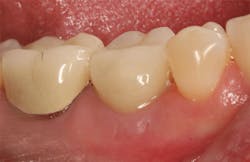

Stage II uncovering was performed five months following the initial surgery. A crestal incision was made toward the lingual ridge to split the keratinized gingiva, as that is where the keratinized gingiva had settled following surgery due to the coronal advancement of the buccal flap to obtain primary closure. The keratinized gingiva was buccally positioned, and a healing abutment was placed. The tissue was sutured with 4.0 chromic gut. This allowed the attached gingiva to heal on the buccal portion of the healing abutment and thus remain on the buccal portion of the final restoration. Final impressions were taken two weeks later, and the restoration was delivered thereafter.

The patient returned three and six months later for a postdelivery radiograph and healing check. The peri-implant tissues were healthy with no abnormal bleeding or probings. The patient reported high satisfaction with his new implant restoration.